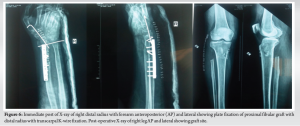

Longitudinal wide excision of right distal radius GCT was planned in view of cortical breach and soft tissue extension. Under general anesthesia, in supine position, incision was made over the dorsal aspect of wrist and forearm. The tumor capsule was identified. Under image intensifier guidance, distal radius was osteotomized. 6.5 cms proximal to distal radius articular surface to give 3 cm of tumor clearance. Using bone holder, the tumor segment with segment of 3 cm of normal bone given for clearance was lifted up (Fig. 5). Care was taken to dissect around the tumor without breaching the tumor. The ligaments of radiocarpal and radioulnar joint were divided and the tumor was delivered out/excised. Proximal fibular autograft including the fibular head was harvested from the ipsilateral right side through the posterolateral approach after isolating the common peroneal nerve. The length of the autograft harvested was around 7 cms. The distal end of this graft was stabilized to the radius with a 3.5 mm Asian dynamic compression plate and screws. Hence, the fibular head resembled and replaced the distal radius. The fibular head was stabilized with two 2 mm Kirschner wires – one fixing it to the carpus and another to the distal ulna (Fig. 6). The patient was maintained on an above elbow slab for 3 weeks and below elbow slab for further 3 weeks. The K-wires and splintage were removed after 6 weeks after which gradual mobilization of wrist and forearm was allowed. The patient was followed up at 3 months, 4 months, 6 months (Fig. 7), and 1 year (Fig. 8) and yearly once after, fibular graft was well united even at 6-month follow-up.

At 2 year and 8 months of follow-up, the patient had (Fig. 9) wrist palmar flexion of 30°, pronation of 70°, supination of 20°, dorsiflexion is NIL. The fibular graft was shorter in comparison to the length of ulna. Probably, if we had taken a longer fibular graft, range of movements may have been better as ulno-carpal impingement could have been avoided. X-ray showed that the fibular graft had well incorporated (Fig. 10).